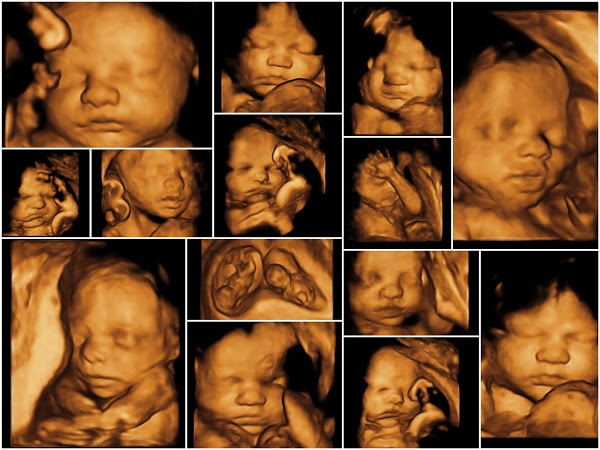

سونوگرافی آنومالی اسکن Anomaly scan

این سونوگرافی نوعی غربالگری است که غربالگری آنومالی جنینی نامیده میشود و به معنی جست وجو درباره مشکلات عمده در آناتومی جنین می باشد و تک تک اعضای حیاتی جنین مثل قلب ، مغز ، کلیه ، معده و ...بررسی میشود تا طبیعی بودنشان تایید شود . در کل هر گونه ناهنجاری را در بدن جنین مشخص می کند و سوراخهای قلب ، بطن های مغز و ... را هم چک میکند.

موارد بررسی سونوگرافی آنومالی اسکن

1- ساختار و شکل سر جنین : بررسی مشکلات مغزی که نادر است .

2- صورت جنین : بررسی شکاف لب و شکاف کام در داخل دهان جنین که به سختی دیده می شود.

3- ستون فقرات جنین : بررسی مقطعی ستون فقرات و طول آن برای اطمینان از هم راستایی استخوان ها و پوشش پوست بر روی ستون فقرات پشت.

4- دیواره شکم جنین : بررسی پوشیده شدن تمام اندام های داخلی با استفاده از دیواره شکم ، همچنین بررسی جفت، بند ناف و آب دور جنین

5- قلب جنین : بررسی دریچه های قلب و رگهای اصلی و شریانها

6- شکم جنین : گاهی جنین مقداری از آب دور خود را قورت می دهد که به صورت حباب های سیاه رنگ در شکم جنین دیده می شود.

7- کلیه های جنین : بررسی کلیه ها ، کالیسها یا لگنچه و … و بررسی حرکت ادرار به داخل مثانه

8- دست ها، پاها و بازوهای جنین : بررسی تعداد انگشتان دست و پاها و چسبندگی آنها و ...

9- معده جنین : گاهی جنین مقداری ازمایع آمنیوتیک که درآن قرار گرفته را قورت میدهد ، که درمعده اش به عنوان یک حباب سیاه دیده می شود.

10- تعیین جنسیت جنین

11- جفت : بررسی موقعیت جفت و نوع و گرید آن و رگهای خونی بندناف

12- مایع آمنیوتیک : بررسی مقدار آب دور جنین تا برای حرکت جنین مقدار کافی آب وجود داشته باشد.